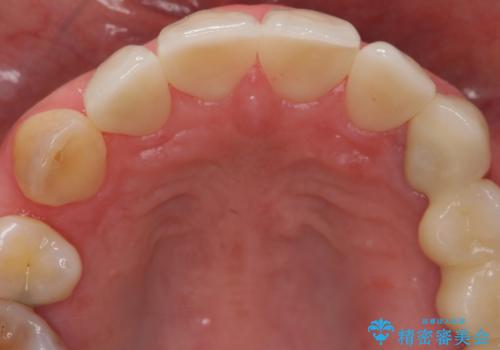

前歯の虫歯 つぎはぎの歯をセラミックに

- 37万円(左上4:e-max クラウン 7万円x4、仮歯 1万円x4 右上2ファイバーコア:2万円x1 プレミアムナイトガード 3万円) 矯正治療は別費用は治療当時の料金となります

下の前歯との距離(クリアランス)が大きくは取れなかったため、ジルコニアクラウンではなくe-maxクラウンにしました。

また、歯ぎしりでセラミックがかけるのを防ぐために、就寝時にはナイトガードを装着してもらっています。